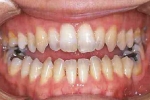

| 治療中

|